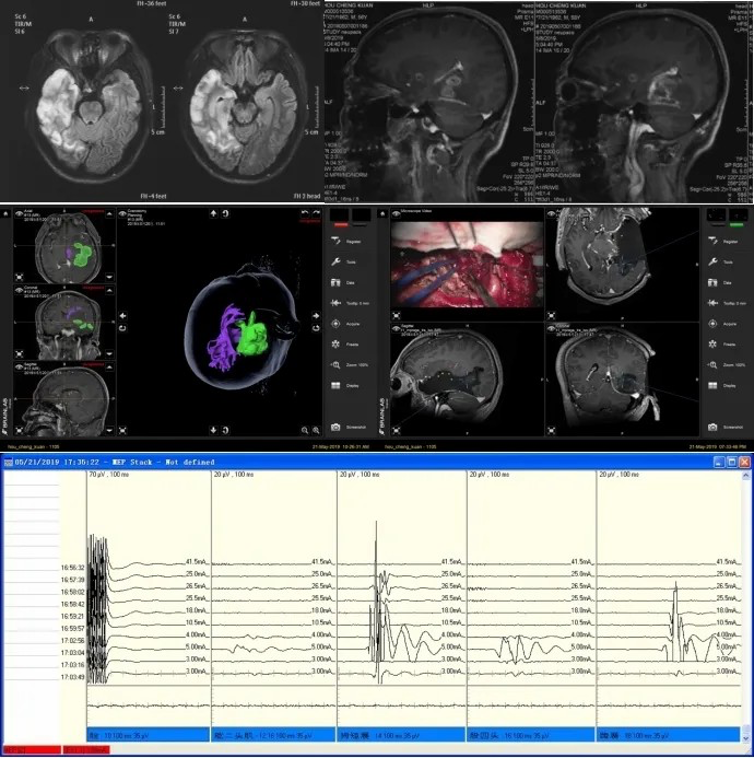

Acoustic neuroma electrophysiological monitoring has been carried out since 2008, and technology has been continuously improved to ensure the preservation of facial nerve function after acoustic neuroma resection. In 2019, the retention rate of the facial nerve in 167 acoustic neuroma surgeries had reached 97%; Using intraoperative MRI and navigation technology, we have carried out subcortical electrical stimulation to locate the relative boundary between the conducting tract and the tumor to ensure that the patient's post-operative movement and sensory function are preserved.

Subcortical electrical stimulation combined with intraoperative image guiding